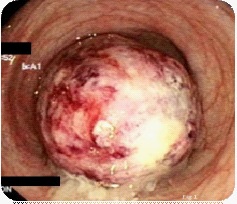

Figure 1: Large ulcerated polyp.

67 years old female no known co-morbids presented to emergency room with episodic severe abdominal pain and vomiting for the last 2 weeks, she brought a CT Abdomen with her which was done a week back, which showed colo-colic intussusception in left colon secondary to possible lipoma as a lead point, initially planned for surgical intervention but patient got better and obstruction was relieved by initial conservative management, she was sheduled for colonoscopy, which showed partially obstructing large pedunculated Kudos 1p polyp in descending colon (Figures 1 and 2). Pros and cons of endoscopic polypectomy were discussed with patient and patient’s family with possible complications of this giant polyp removal was explained in detail, patient and the patient’s family opted for the endoscopic management and informed consent was taken for the same. Elective hot snare en bloc polypectomy was performed uneventfully entire polyp of 7 X 3.5 X 3 cm (Figure 4) was retrieved successfully. The post endoscopic period went uneventful and histology confirms the diagnosis of lipoma. Patient visited our outpatient clinic at 2 weeks and 4 weeks post procedure, she remained well throughout with no abdominal pain and no drop in haemoglobin.